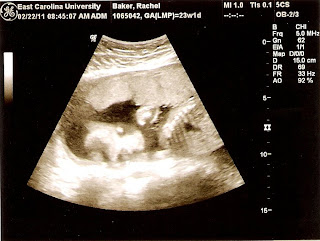

The object of this ultrasound was to get better head measurements, because Elizabeth was less than cooperative the last time. Thus, most of the focus was on trying to get good shots of her head. She wasn't as cooperative as the doctor would have liked, but the measurements were procured. Elizabeth is just over a pound, which is normal for her gestational age of 23 weeks. At my check-up, everything looks good for me, too--blood pressure, heart rate, etc., all within normal parameters. I likely have the infamous glucose test to look forward to at my next visit.